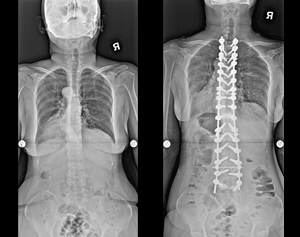

病例三 |

| 術前 |

術後 |

| 正向X光片 |